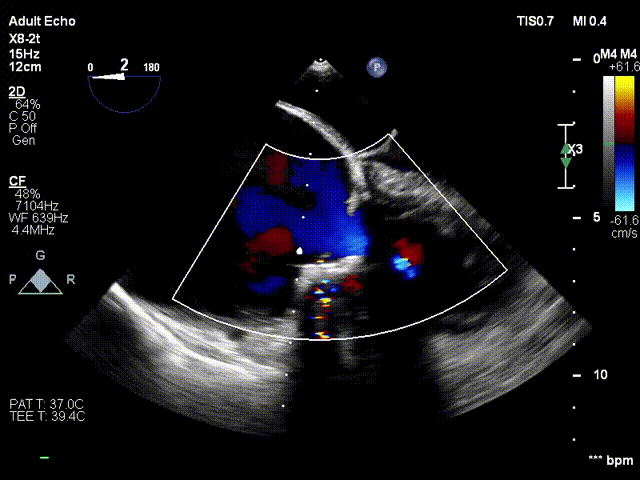

术后食道超声显示球扩瓣形态理想、反流消失